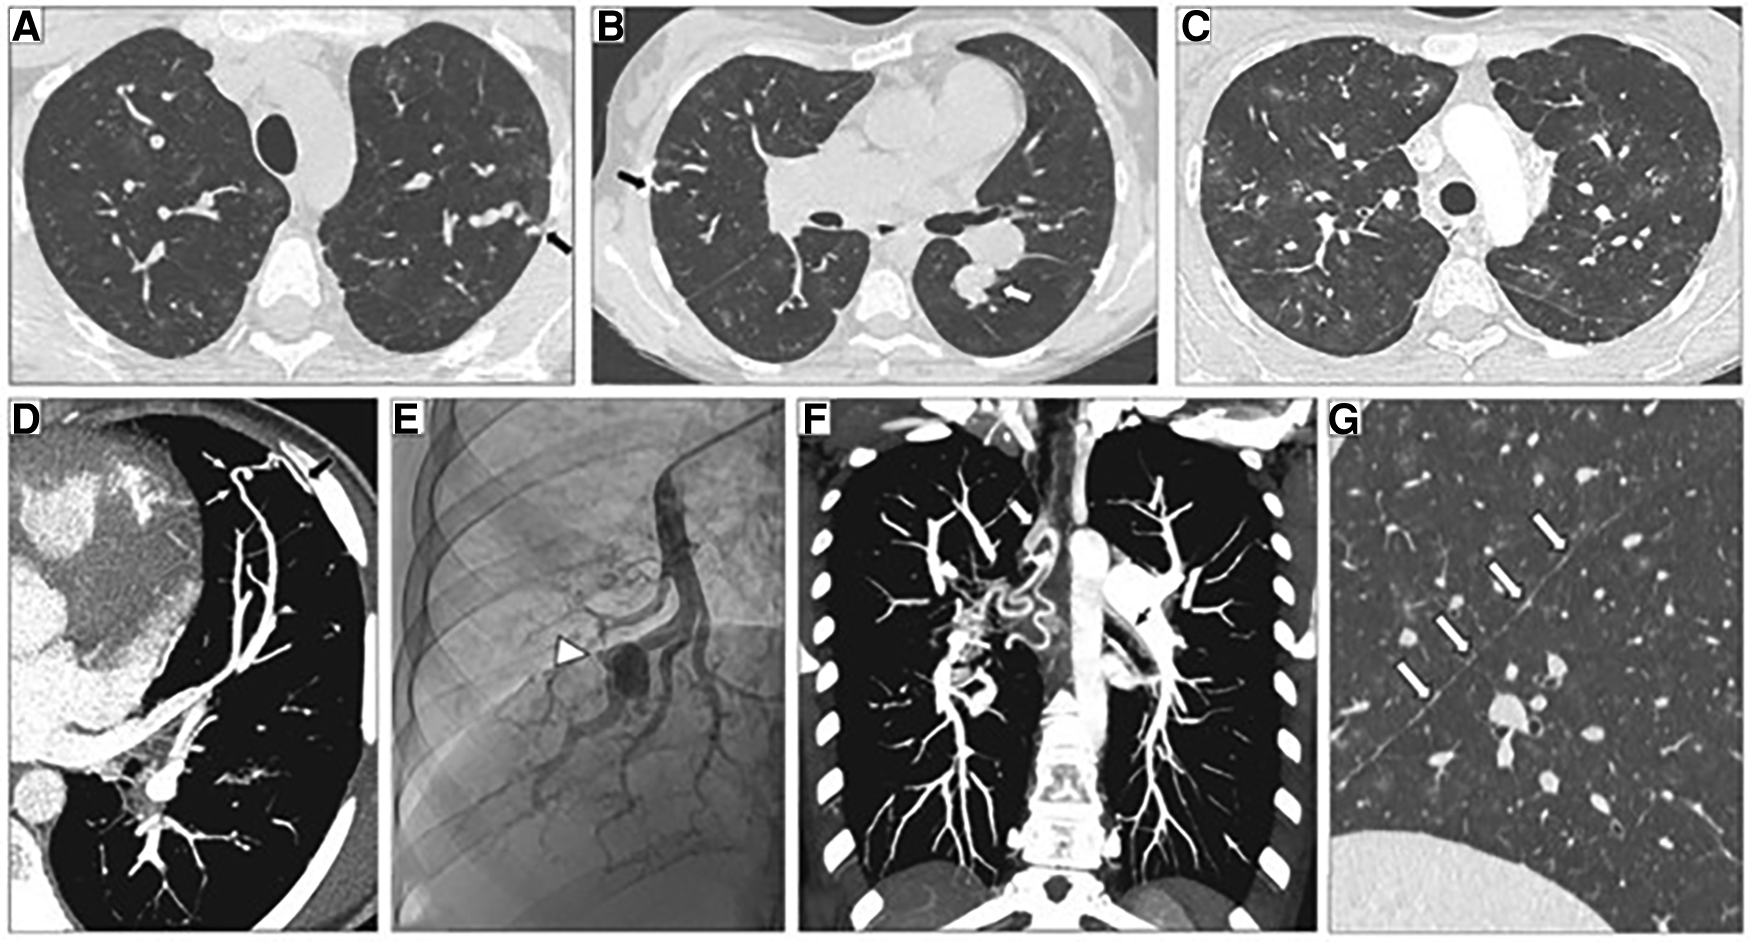

Figure 6

Representative high-resolution computed tomography (HRCT) of the chest, CT pulmonary angiography (CTPA) and pulmonary angiogram of pulmonary arterial hypertension patients carrying a SOX17 pathogenic variant. (A–C) Thin-collimated HRCT of the chest showing (A,B) subpleural dilated and tortuous pulmonary vessels (black arrows) and (C) ground-glass opacities. (D) The black arrow points to direct communication between a dilated distal pulmonary artery and a dilated intercostal artery. (B,E) Aneurysmal dilatation identified on b) CTPA (white arrow) and (E) pulmonary angiography (arrowhead). (F) Marked dilatation of proximal bronchial arteries is frequently observed (white and black arrows). (G) The presence of numerous fissural irregularities (white arrows) suggests the additional presence of dilated systemic vessels at the pleural surface. Reproduced from Montani et al., 2022.